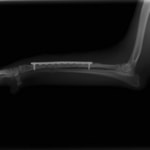

トイプードル 右遠位橈尺骨短斜骨折のALPSによる内固定